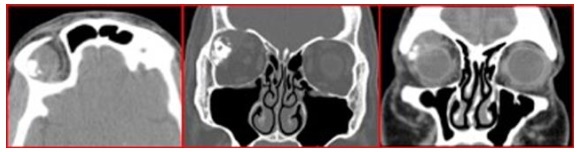

45 yo M pain right orbit x 9 months. Next step

incisional biopsy of lacrimal gland

lacrimal gland with calcification and adjacent bony thinning/erosion

adenoid cystic carcinoma